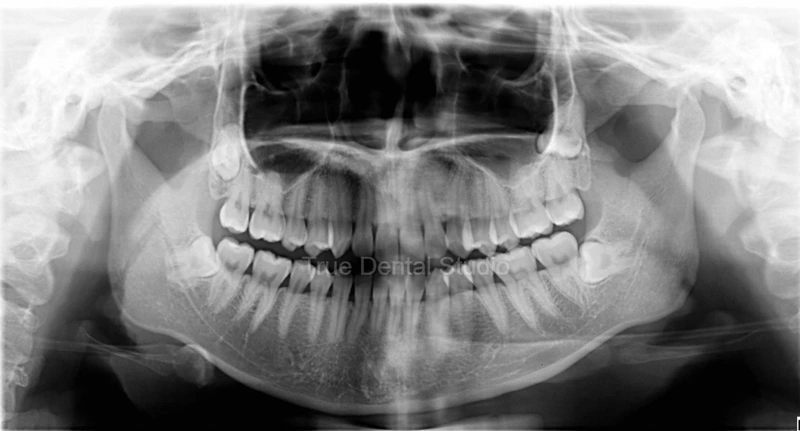

Panoramic image of orthopantomogram (OPG) X-Ray of patient's teeth.

Orthopantomogram (OPG) X-Ray image of patient's teeth.

Case 1: Patient A underwent an orthopantomogram (OPG) X-Ray as a preliminary diagnostic step before starting Invisalign treatment. The OPG was conducted to assess the patient's overall oral health prior to initiating the aesthetic correction procedure.